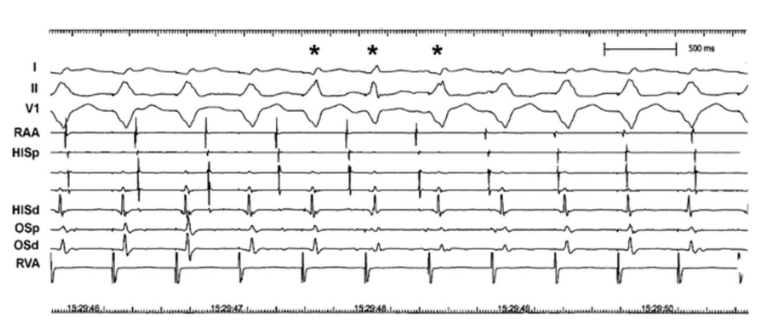

The ventricular PCL is initiated with a CL slightly shorter than the sinus. Rather than seeing the atria develop any relationship with the ventricular paced beats, AV dissociation is observed instead: the P waves just march through the QRS complexes (Figure 13).

Since the sinus and ventricular paced rhythms are not synchronous and have different rates, their timing relationship changes. Intermittently, the timing relationship between A and V aligns in such a way that antegrade conduction of the sinus beat is reassociated with the ventricles. This produces a “capture” beat.

If the ventricular rhythm is slow enough, the sinus impulse may have a better chance to capture the ventricles and may produce a narrow QRS

complex; when the ventricular CL is shorter, the captured ventricular beat may coincide with a paced ventricular beat, resulting in “fusion” of the two. The 3 beats labeled with an asterisk denote such fusion. The fusion in the first and third beats is more subtle (note lead II QRS morphology difference) than in the second.

Fusion beats always arise from capture in the setting of DVP, but not all capture beats are narrow. Capture and fusion are unequivocally diagnostic of AV dissociation.n